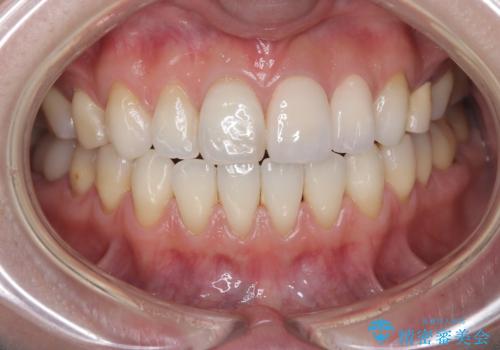

- 「前歯の色が気になる」を主訴に来院された患者さんです。以前他院にて、前歯2本をCR(プラスチック)で治療されていたところが劣化し変色していました。歯の長さも左右で異なっている状態でした。大部分がCR(プラスチック)修復されていたので、オールセラミッククラウンで治療を行いました。

- 費用(概算)

- 30万8千円(オールセラミッククラウンスペシャル14万3千円×2本 仮歯1万1千円×2本) ※改定前の価格費用は治療当時の料金となります

古いCR(プラスチック)とその下の虫歯を除去した後に新しい土台を立てています。適合が良い被せ物を作るために拡大鏡を使用しながら歯を削り、変形のほとんどないシリコンという材料で型取りを行っています。